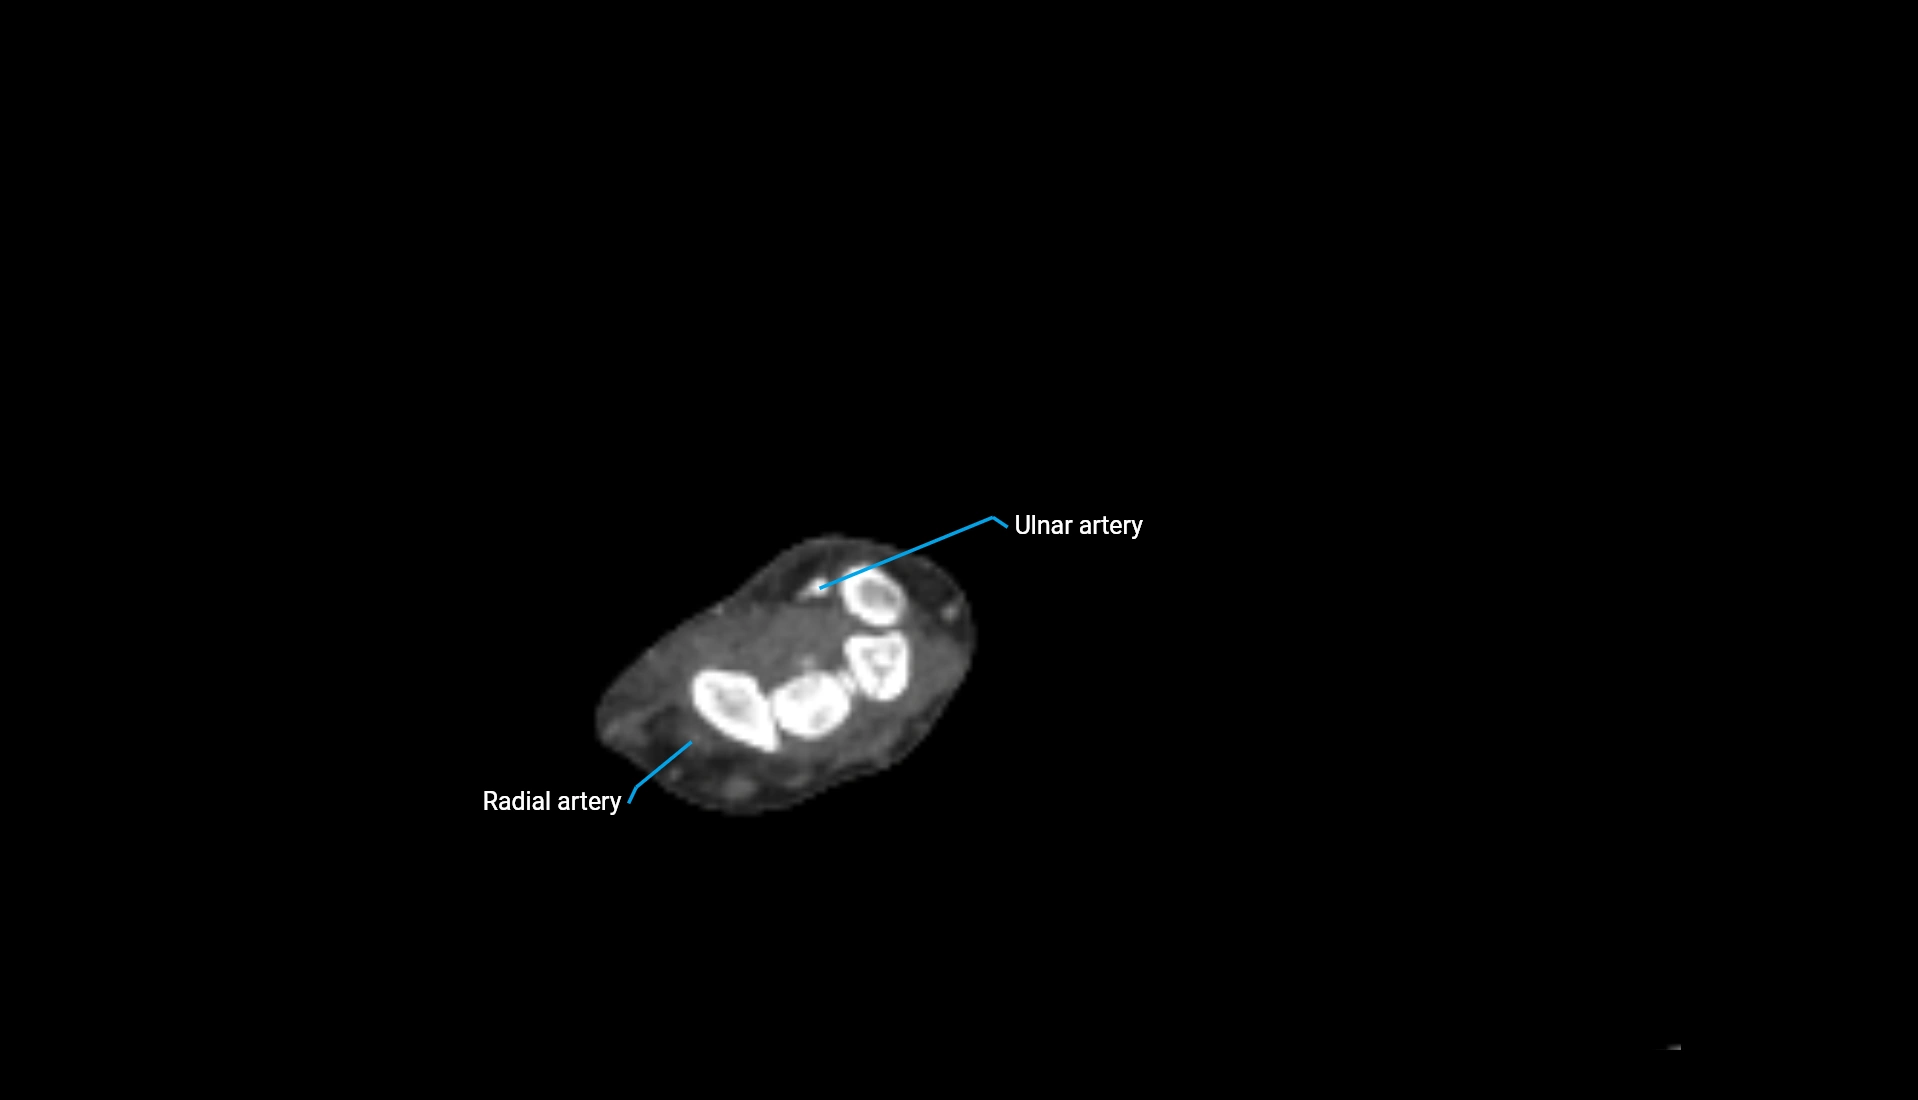

CT Appearance

Non-Contrast CT:

• Cortex: High-density, sharply defined

• Subchondral bone: Dense cancellous matrix

• Articular surface: Smooth concave contour articulating with the capitellum

• Excellent for evaluating bone integrity, alignment, and subtle fractures